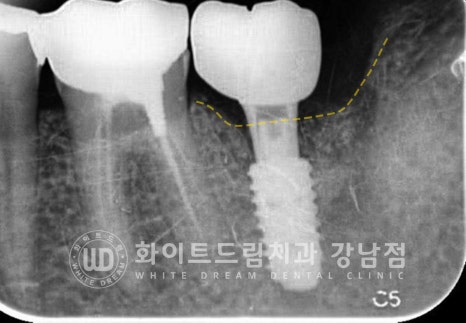

임플란트의 상태를 보니 주위 염증이 심하게 발생하고

잇몸뼈도 많이 녹아내린 상태이며 임플란트 끝부분이 잇몸뼈에 겨우 붙어 있는 상태였습니다.

보통 주위염이 발생하면 1/3 정도까지는 잇몸치료를 통해 조금 더 사용할 수 있게 하지만

이렇게 2/3 이상의 잇몸뼈가 녹은 경우는 대부분 임플란트 제거 후 재식립을 고려하게 됩니다.